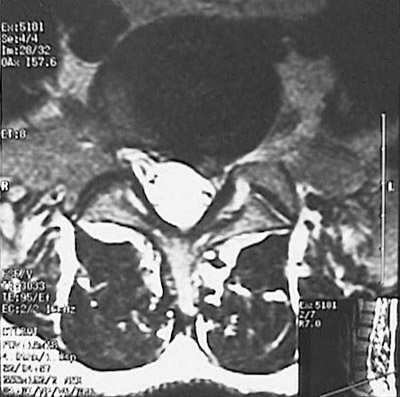

This MRI of the spine demonstrates herniation of the nucleus pulposis of the intervertebral disc between L5 and S1 with compression of the lumbar spinal cord. Such a herniated disc can compress spinal nerve roots to produce pain and/or motor weakness. In the transverse view below, the herniation is seen to compress the nerve roots on the left. |